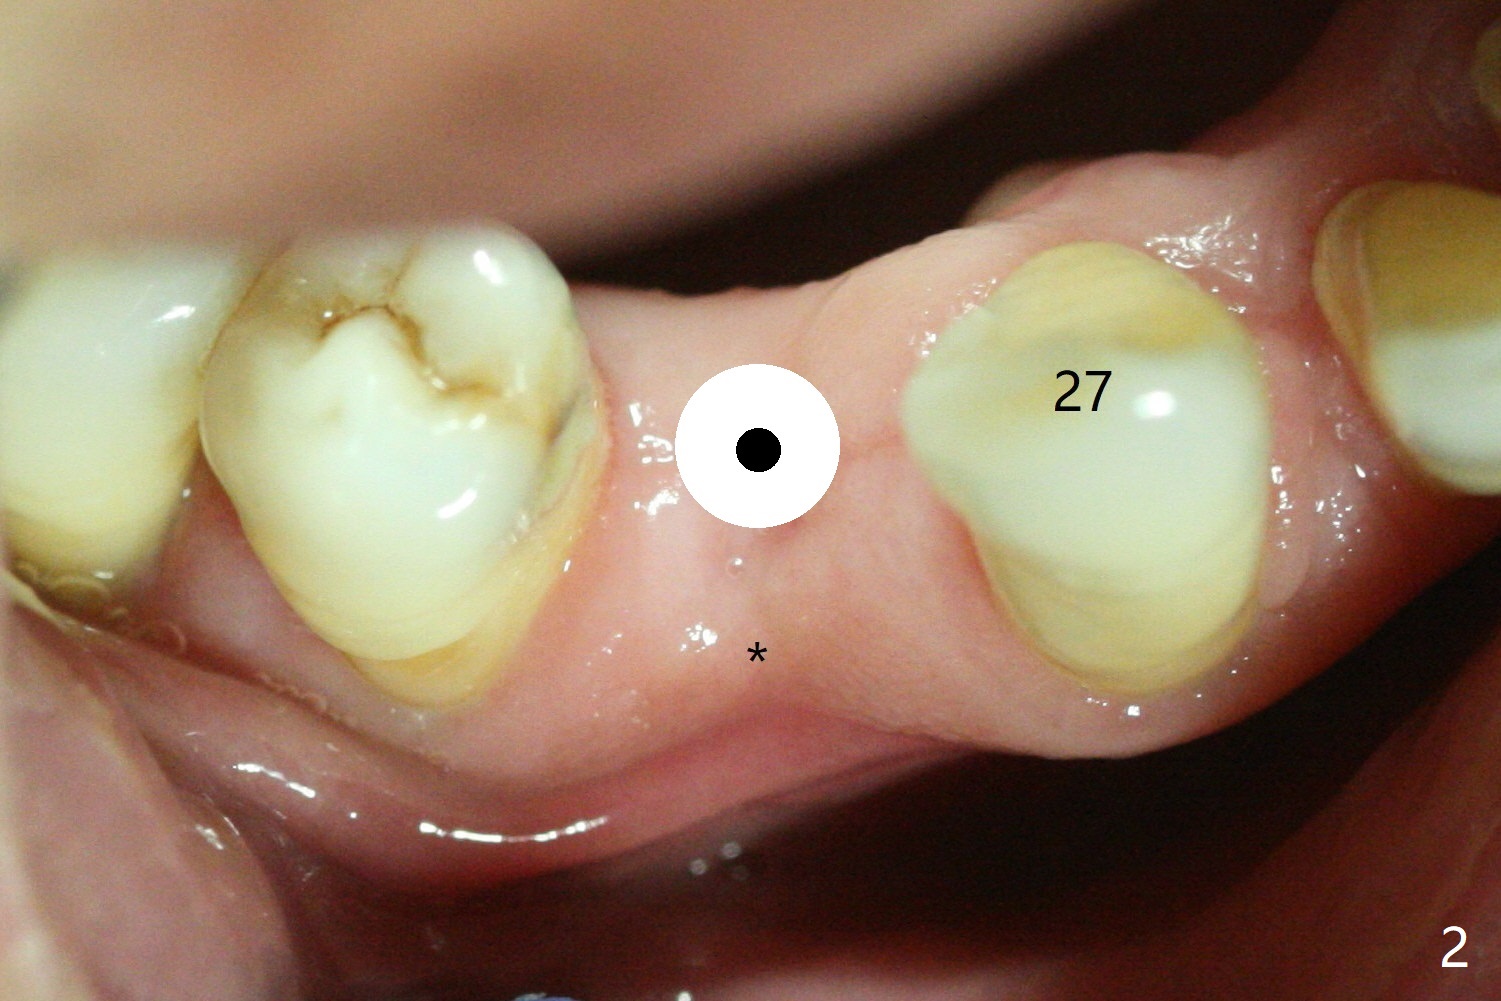

Surgery begins with tissue punch or pointed drill

(Fig.1 white circle) through surgical guide at #28 with the concave buccal plate

(*), followed by initial osteotomy using 2.2 mm drill with guide (Fig.2 small